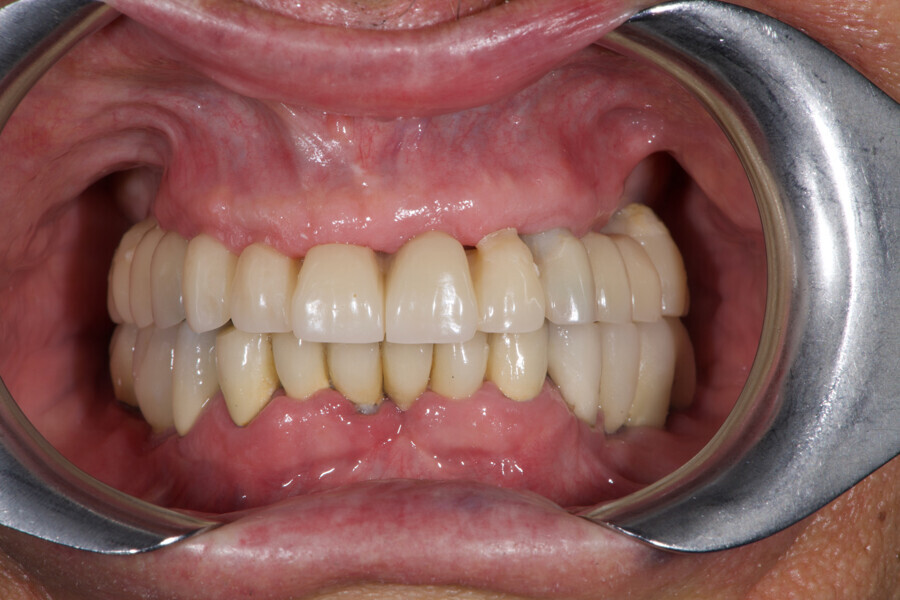

At the final appointment, the definitive hybrid screw-retained prosthesis was delivered. The definitive prosthesis consisted of a CAD/CAM titanium framework screwed on to all of the implants and three monolithic zirconia prosthetic segments bonded on top (Figs. 18a–c). The occlusion was evaluated, and the patient was enrolled in a four-month maintenance programme. At the last follow-up (one year after implant placement), all of the implants were successful and the patient was fully satisfied with the new prosthesis (Figs. 19–22).